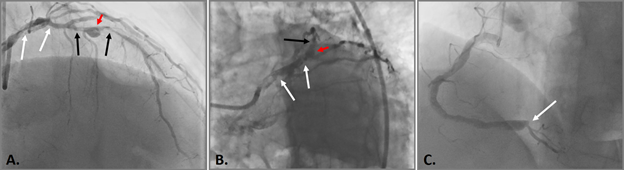

The patient underwent endovascular rotational atherectomy followed by stenting of the affected segments of the coronary arteries. The intervention was carried out under the control of optical coherence tomography (OCT). Initially, the right common femoral artery was punctured under local anesthesia and a 7F introducer was placed. Next, the guide catheter was placed at the mouth of the LCA. The coronarogram revealed 80% calcified stenosis in the terminal LCA OS with a transition to the proximal segment of the LAD and 90% calcified stenosis in the middle segment of the LAD (Figure 1). Using a microcatheter, a conductor was introduced into the apical segment of the LAD. Next, the destruction of calcified atherosclerotic plaques in the LCA and LAD was performed using the Rotablator system of rotational atherectomy (Figure 2), after which, under OCT control (Figure 3), predilatation of the stenotic areas of the LAD with a 2.25x15 mm balloon catheter was performed, followed by positioning and implantation in the area of residual stenoses in the middle segment of the LAD, the proximal segment of the LAD and the OS of the LCA of everolimus drug-eluting stents 3x38 mm and 4x38 mm, respectively. Then, post-dilatation of the stented segments with 3.5x20 mm, 4.5x15 mm balloon catheters and proximal optimization in the LCA OS with a 5x15 mm balloon catheter were performed, achieving a good angiographic result: blood flow in the TIMI-3 arteries. On the control image and OCT control, the stents were fully extended, no signs of dissection were detected, and no residual stenoses were found (Figure 4, 5).

Figure 1 Selective coronary angiography.

A. and B. 80% calcified stenosis in the terminal LCA and proximal LAD segment (white arrows), 90% calcified stenosis in the middle LAD segment (black arrows) and aneurysm in the middle LAD segment with a diameter of up to 6 mm (red arrow); C. RCA is diffusely changed, expanded throughout up to 5-6 mm; VZV is occluded from the orifice (white arrow).